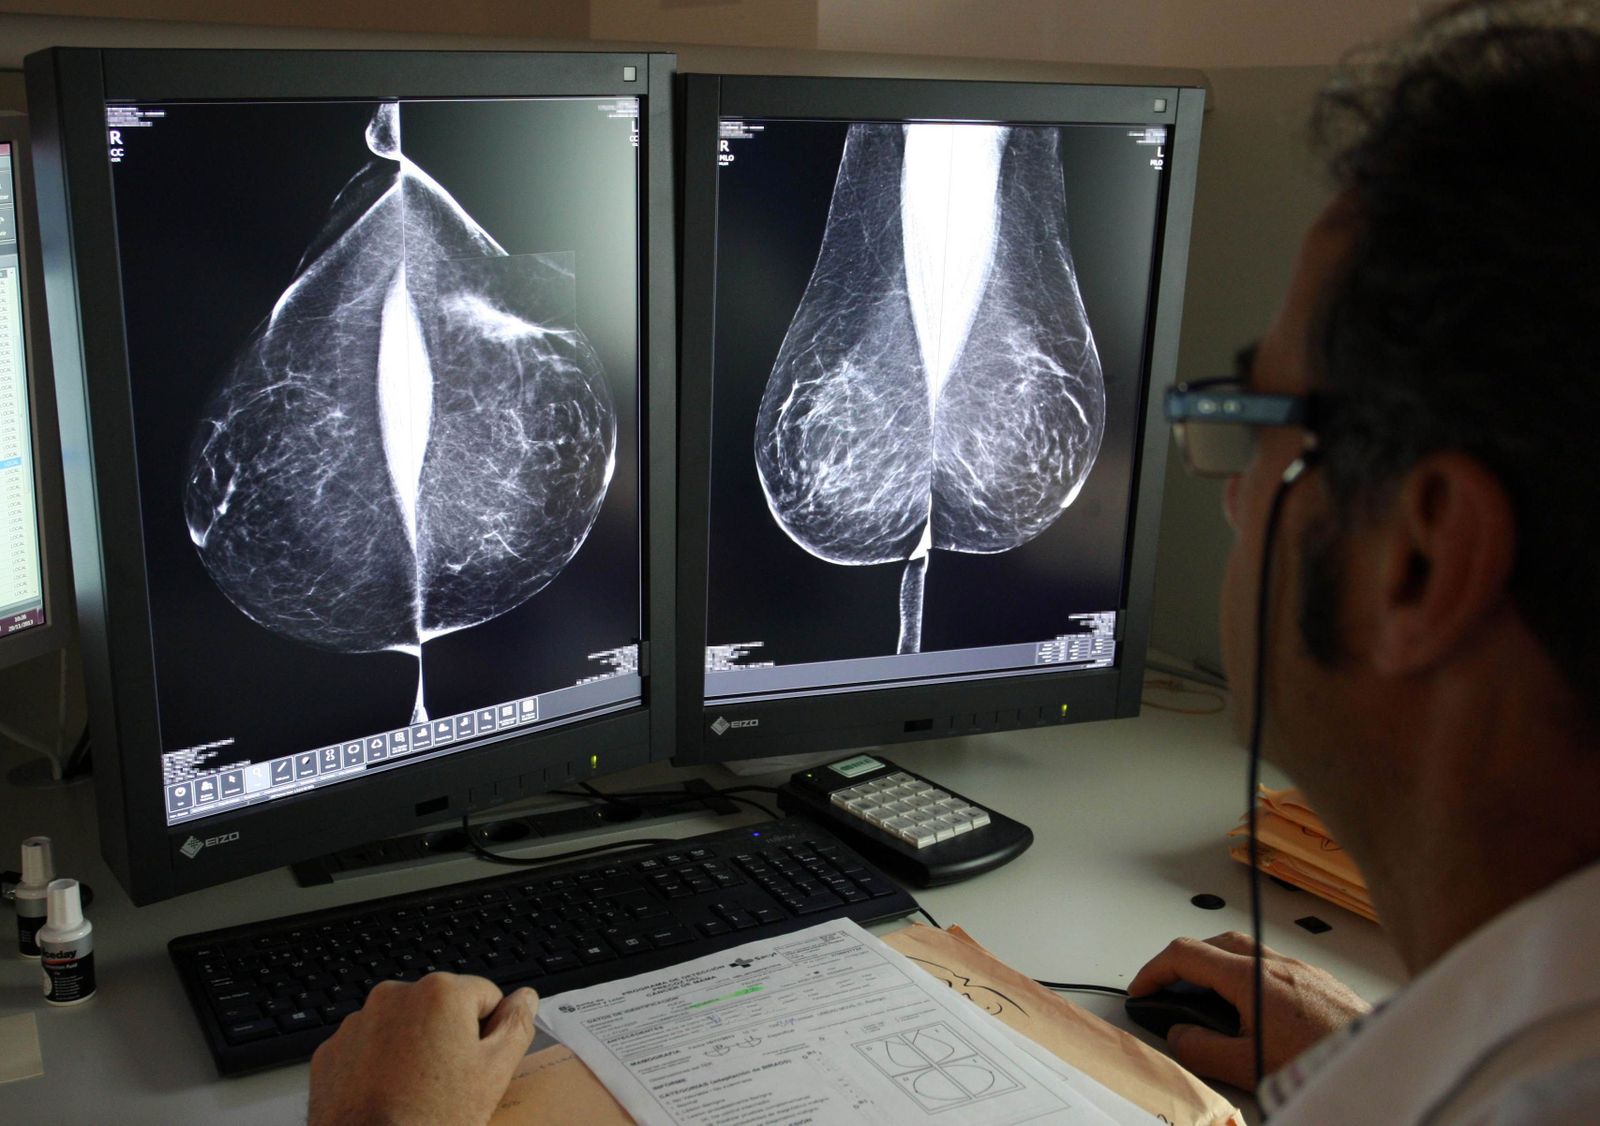

Rubén Cacho. Estudio de una mamografía digital en el servicio de mamografías del Hospital Río Hortega de Valladolid

Está demostrado que las mamografías son la mejor prueba de detección precoz existente en la actualidad, ya que gracias a ellas pueden detectarse entre el 90 y 95 por ciento de los tumores por muy pequeños que sean, lo que permite disminuir la mortalidad por esta causa y aumentar la calidad de vida de las mujeres afectadas. Consiste en una radiografía, con bajos niveles de radiación, que dura pocos segundos y que se repite cada dos años.